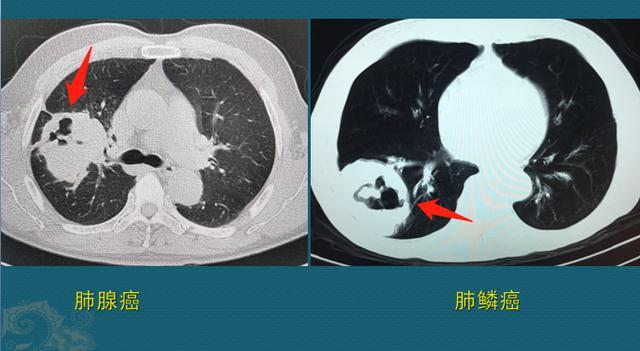

肺结核与肺癌像“真假美猴王”,医生教你用CT片当照妖镜,找不同

没办法,很多医生把肺结核称作“妖”,结核杆菌与身体免疫力在肺脏大战三百回合之后,就像真假美猴王,会把战场搞出72种变化,有的像肺炎、有的像肺癌

我们看几张CT图片,看看唐三藏遇上真假美猴王,紧箍咒是如何失效的